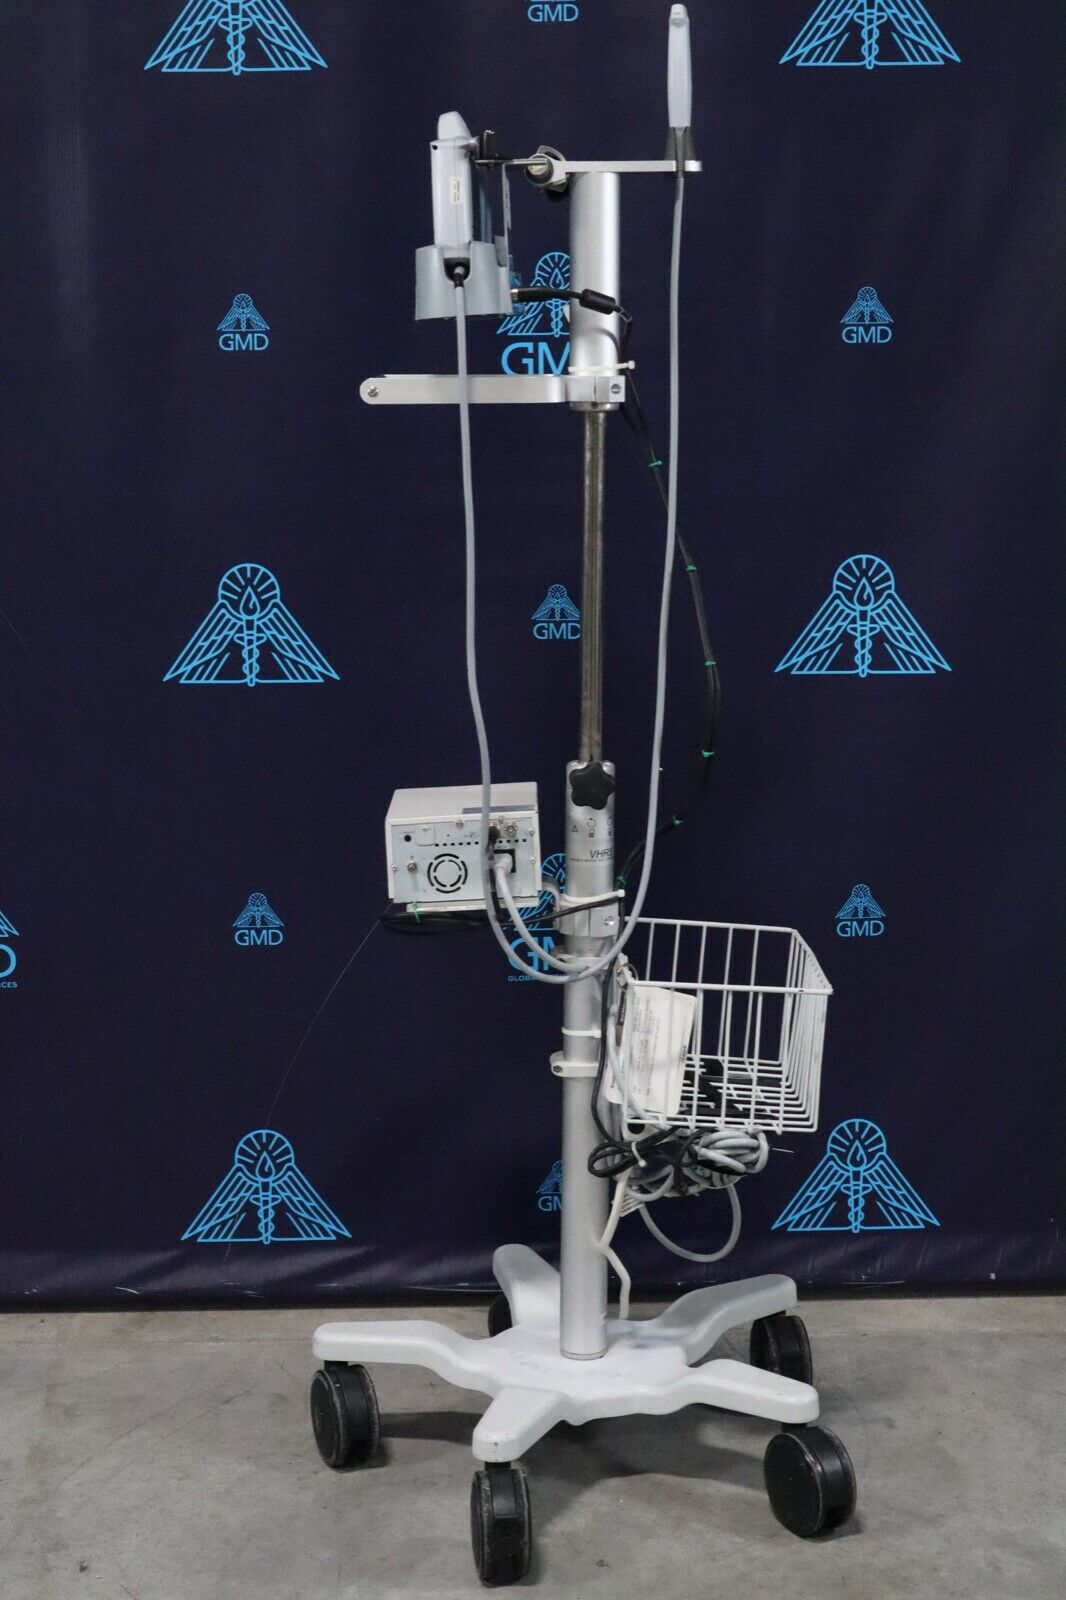

Sonosite S-Nerve vascular/nerve Ultrasound with Cart

Sale price$ 28,781.98